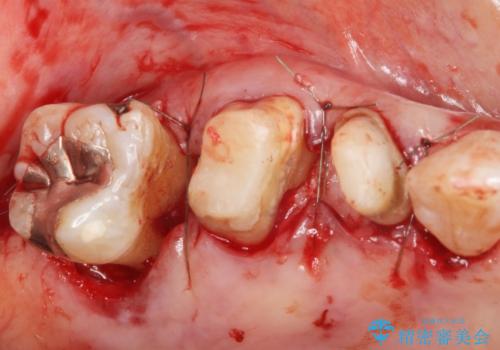

「抜歯したくない、インプラントは嫌」という患者様のご希望とご年齢を考慮し、可及的な骨外科処置や根分割術によりできるだけ今ある歯を残す治療方針をたてました。

長期的な予後は保証できないことをご了承頂いた上で治療を行いました。

ご希望により、積極的な再根管治療は行いませんでした。

- 外科手術のため、術後に痛みや腫れ、違和感を伴います

- 歯周組織再生治療は患者様の状態によって術後の経過が異なります(見た目が改善しない場合もあります)